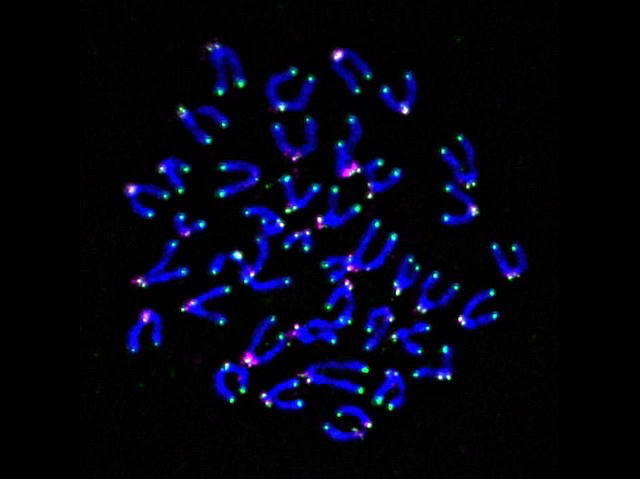

Aquests garbuixos blaus són els cromosomes d’una cèl·lula immunitària de ratolí (concretament, un limfòcit T) i els telòmers (les seqüències repetitives d’ADN als extrems dels cromosomes) estan ressaltats en verd. Els telòmers són un bon indicador de la salut cel·lular: la seua degradació i pèrdua indiquen un deteriorament de la funció de la cèl·lula. Les espècies reactives d’oxigen (abreviat com a ROS), que danyen l’ADN, poden provocar aquesta degradació dels telòmers i, malauradament, això és exactament el que passa als limfòcits T dins d’un tumor, on abunden estímuls estressants que induïxen ROS, com ara la baixa concentració d’oxigen o una elevada acidesa. Com que els limfòcits T poden reconèixer i destruir cèl·lules canceroses, mantindre la funció és essencial. El més important és que els investigadors han demostrat que, si s’administra un antioxidant dirigit específicament als telòmers dels limfòcits T, es pot evitar la seua disfunció. A més, quan aquests limfòcits T amb els telòmers protegits, es van infondre en ratolins amb melanoma, els tumors dels animals van ser més menuts que els dels ratolins de control i la seua supervivència va millorar.